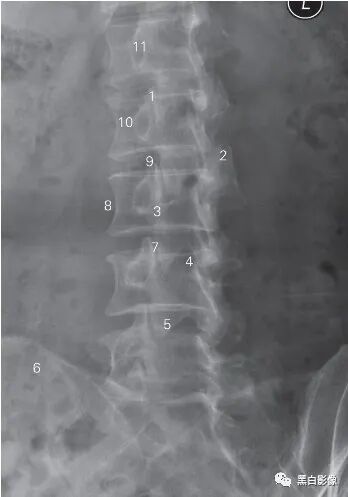

图6-5 腰椎侧位DR 平片

1 上关节突 superior articular process 2 下关节突 inferior articular process

3 椎间孔 foramen intervertebrale 4 棘突 spinous process

5 关节突关节 zygapophyseal joint 6 髂骨 ilium

7 骶骨 sacrum 8 第5腰椎 5th lumbar vertebra

9 椎弓峡部 isthmus vertebral arch

10 L2/3椎间隙 L2/3 lumber intervertebrale space

11 第1腰椎椎体 1st lumbar vertebral body